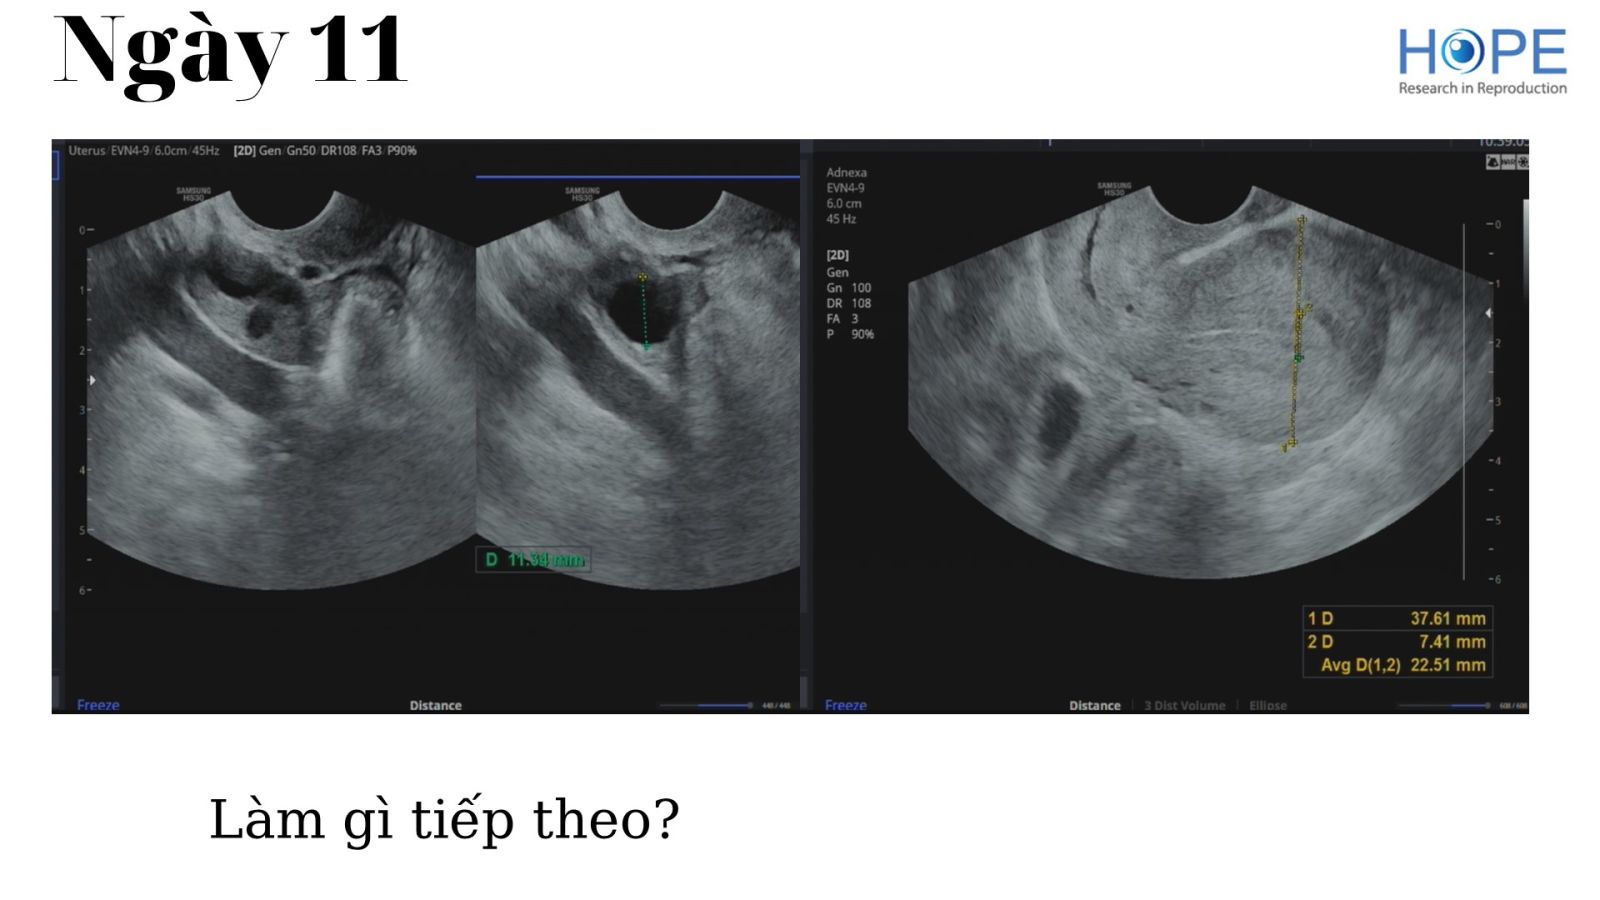

Các phác đồ kích thích buồng trứng nhẹ để IUI –  cách theo dõi kích thích buồng trứng

BS Lê Thị Hà Xuyên - IVFMD Phú Nhuận